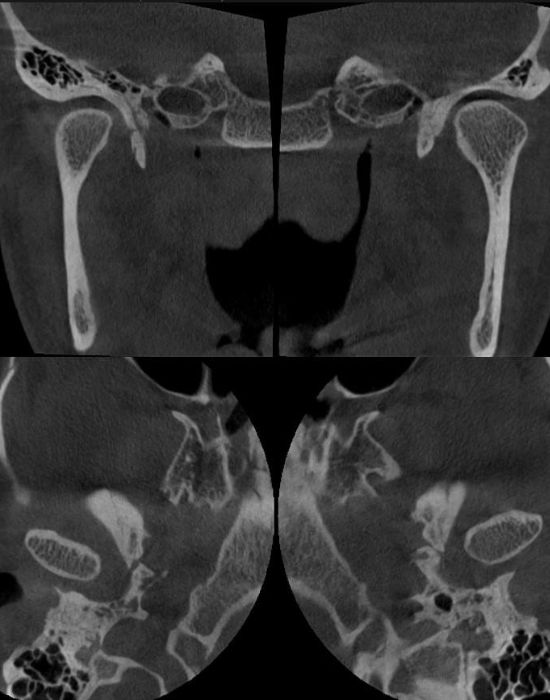

Скронево-нижньощелепний суглоб: стандарти рентгенологічних досліджень для лаборантів